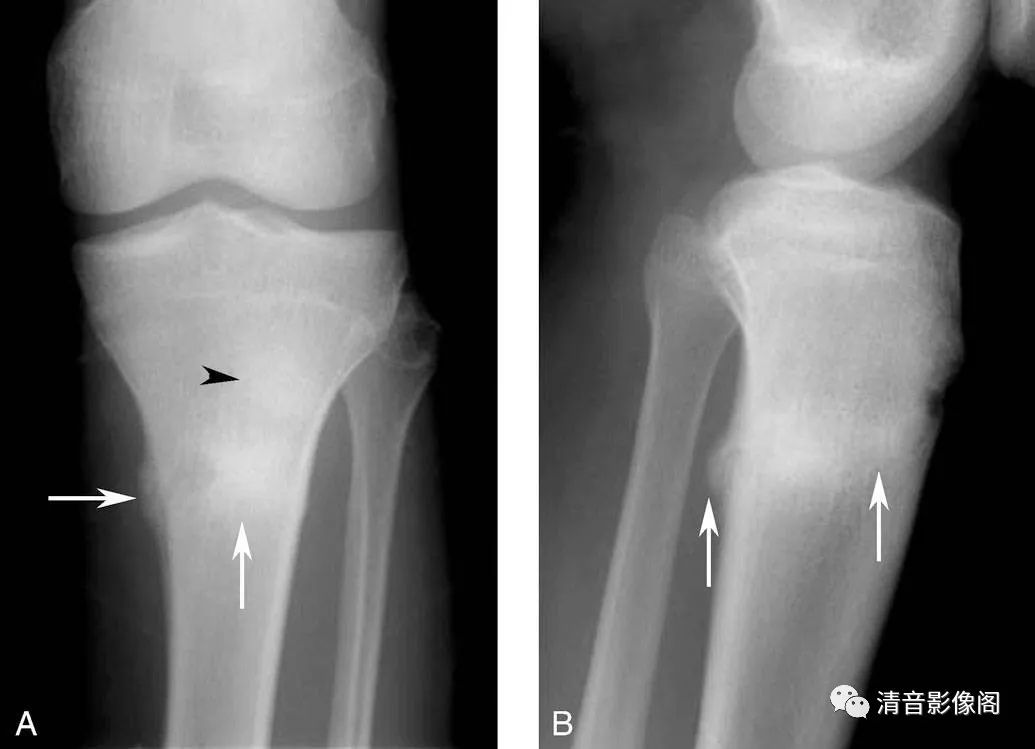

胫骨应力骨折

A. 左膝关节X线正位;B. 左膝关节X线侧位。胫骨干与干骺交界区横行宽带状高密度影,为修复的骨痂。高密度影中见透亮线(箭),为骨折线。胫前结节位于病灶上方,呈高密度影(黑箭头)。